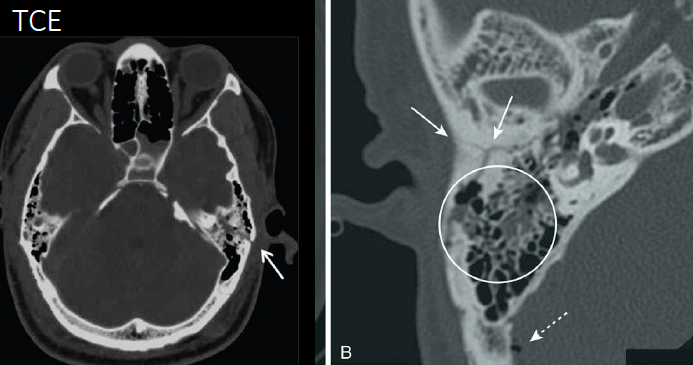

TCE

¿Qué tipo de fractura es esta?

A

Fractura de base de cráneo